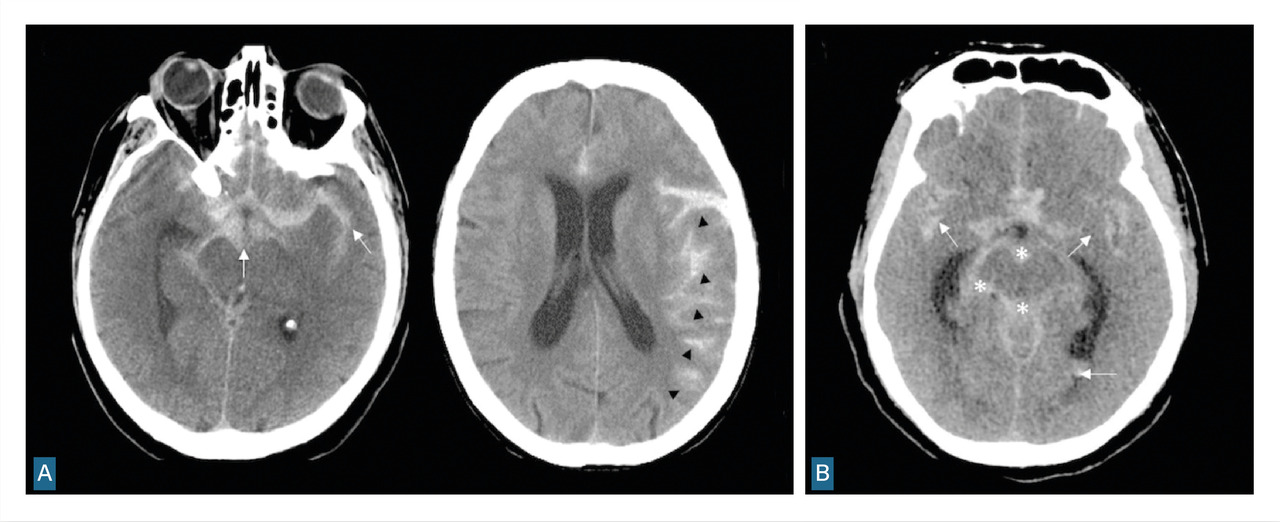

Le scanner doit être réalisé en urgence. Il montre une hyperdensité des espaces sous-arachnoïdiens, évalue la sévérité par l’échelle de Fisher et recherche les complications précoces (fig. 1 et tableau 1).